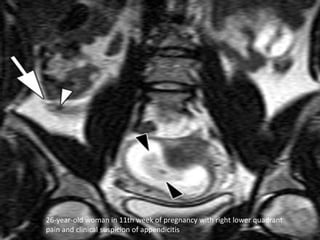

26-year-old woman in 11th week of pregnancy with right lower quadrant

pain and clinical suspicion of appendicitis

• Imaging modalities –Negative appendectomy rate: -Clinical diagnosis alone: 54% -Clinical, US & CT: 8%  1st Line:  US  2nd line:  CT (sensitivity 98%; specificity 98%)  MRI (sensitivity 100%)

26-year-old woman in11th week of pregnancy with right lower quadrant pain and clinical suspicion of appendicitis